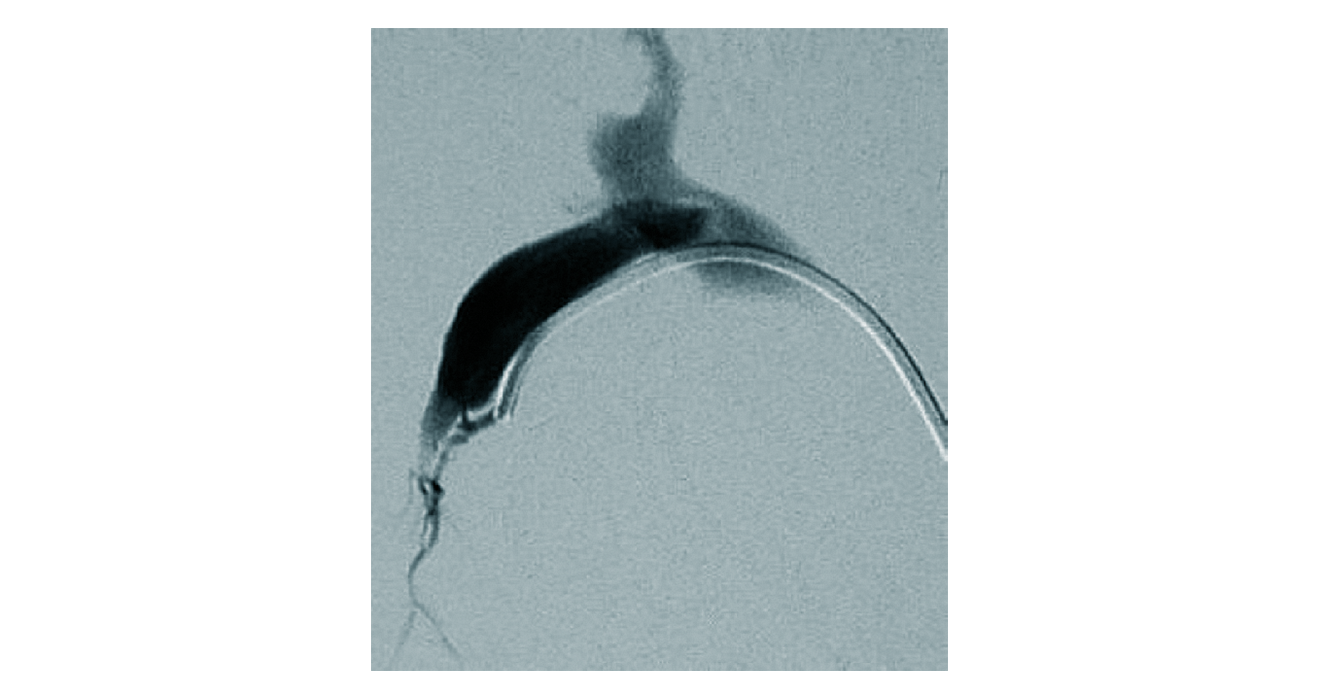

Figure 2. Spontaneous arterioportal shunt. Angiography in a patient with non-cirrhotic portal hypertension. A small arterioportal shunt is detected by superselective catheterisation of the hepatic artery